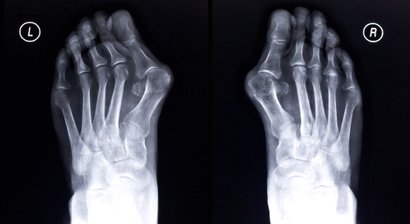

Wenn ein chirurgischer Eingriff notwendig ist, so finden Sie in mir einen Spezialisten für Operationen an Hüfte, Knie und Schulter sowie im Hand- und Fußbereich. Dabei setze ich auf schonende minimal-invasive Methoden.

Fußchirurgie

OP der linken großen Zehe

Nach den beiden Hüftoperationen, welche von Dr. Cetin bestens durchgeführt wurden, wurde auch diese OP wieder hervorragend durchgeführt.

Ich bedanke mich beim Herr Dr. Cetin und kann sagen, man ist in besten Händen!!!!